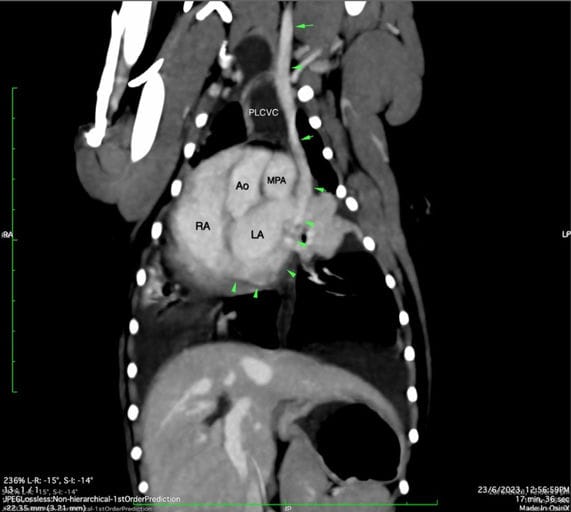

Three days postoperatively, the dog developed dyspnoea due to bilateral chylous pleural effusion. Computed tomography identified the aberrant vessel as a complete PLCVC draining into the right atrium, with a normal right cranial vena cava also present. No evidence of thrombosis or permanent vascular obstruction was detected. Chylothorax resolved spontaneously following thoracostomy tube placement, without additional surgical or medical intervention. Follow-up echocardiography eight weeks later demonstrated normal cardiac dimensions and flow patterns, with resolution of preoperative cardiac changes.

Dorsal multiplanar reconstruction showing trajectory (green arrowheads) of persistent left cranial vena cava (PLCVC) caudal to heart and inserting into right atrium (RA). Ao, aorta; LA, left atrium; MPA, main pulmonary artery.